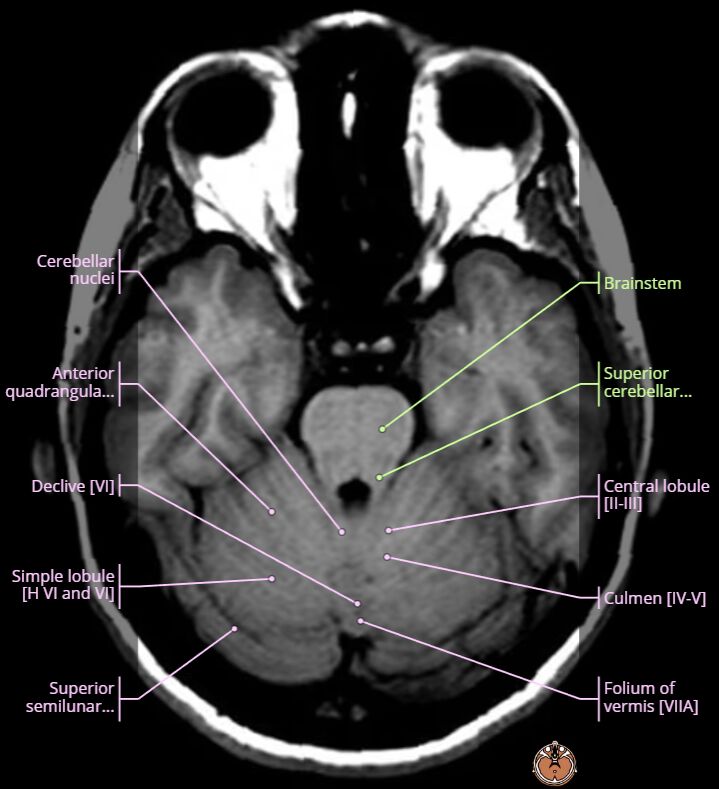

題目右上角的黑色圓形空洞,是眼睛,切片高度的重要landmark如下圖:

對照可知,白色出血區域是左側小腦